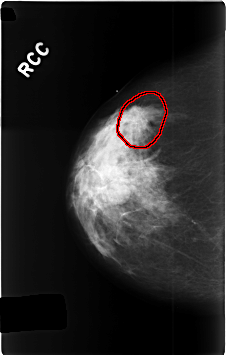

C_0339_1.RIGHT_CC

FILE: C_0339_1.RIGHT_CC.OVERLAY

TOTAL_ABNORMALITIES 1

ABNORMALITY 1

LESION_TYPE MASS SHAPE ROUND MARGINS SPICULATED

ASSESSMENT 5

SUBTLETY 5

PATHOLOGY MALIGNANT

TOTAL_OUTLINES 1

BOUNDARY